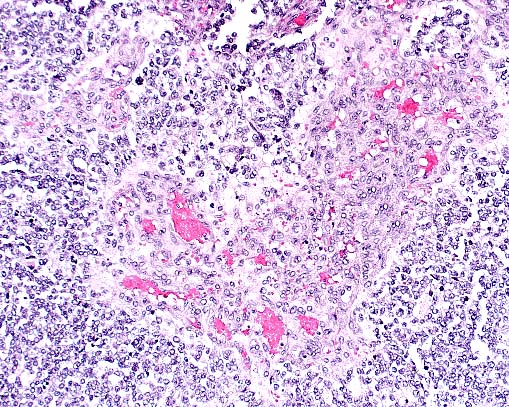

Case II - MK96-1859 (AFIP 2550320)

Signalment: Adult female tamarin.

Necrotizing colitis in a tamarin monkey. (HE, 40X, 73K)

Multinucleate viral syncytial cell in crypt in a tamarin infected with measles virus. (HE, 400X, 66K)

Crypt herniation in a measles-infected tamarin. (HE, 100X, 106K)

History: A wild-caught female tamarin, housed in a biomedical research colony, was found dead. She had experienced severe diarrhea, which responded temporarily to supportive therapy (fluids and karo syrup).

Gross Pathology: The monkey is mildly dehydrated, with normal muscle mass and scant body fat stores. The parietal peritoneum is mildly thickened, with a granular appearance. Multiple filariid nematodes are present within the abdominal cavity. Multiple 3-4 mm nodules are visible from the serosa of the terminal ileum; these are diverticula of the mucosa, many of which contain embedded heads of acanthocephalid parasites. Numerous acanthocephalids are also attached to the mucosa of the cecum and the cecal-colic junction. The mucosa of the cecum and colon is reddened, and mesenteric lymph nodes are mildly enlarged. There is mucoid fluid in the stomach and normal ingesta in the small intestines and cecum; the colon is empty.

Laboratory Results: Campylobacter sp. was recovered from the colon. The intra-abdominal filarid nematodes were identified as Dipetalonema sp. The acanthocephalids were identified as Prosthenorchis elegans. Additionally, tapeworm proglottids were found in the intestinal contents.

The colon was positive for measles antigen by immunohistochemistry, using a "measles blend", a combination of 2 monoclonal antibodies directed against measles hemagglutinin and matrix protein (Chemicon International, Inc., catalog #MAB8920).

Contributor's Diagnosis and Comments: Colon: Colitis, acute, diffuse, moderate, with epithelial syncytial cells and intranuclear inclusion bodies. Etiology: Paramyxovirus infection, most likely measles.

The histologic changes in the colon (epithelial necrosis, epithelial syncytial cells and intranuclear inclusion bodies) are consistent with infection with a paramyxovirus. A careful microscopic search of multiple organs, including spleen, liver, lymph nodes and lung failed to demonstrate involvement of any other organ. Callitrichids are susceptible to parainfluenza virus, measles (morbillivirus) virus, and Paramyxovirus saguinus. Parainfluenza is characterized clinically by upper and lower respiratory tract disease. Measles in New World primates can manifest as a respiratory tract disease or an enteritis. Paramyxovirus saguinus is reported to cause gastroenteritis in marmosets and tamarins.

AFIP Diagnosis: Colon: Colitis, necrotizing, subacute, diffuse, moderate, with crypt herniation, lymphoid depletion, syncytial cells, and intranuclear and intracytoplasmic inclusion bodies, tamarin, primate.

Conference Note: Using formalin-fixed paraffin-embedded colon from this monkey, the Department of Cellular Pathology of the AFIP detected morbilliviral RNA by reverse transcriptase polymerase chain reaction. Southern blot using a measles virus-specific probe was positive confirming that measles virus was the etiologic agent.

Measles virus is a morbillivirus of the paramyxovirus family. It has an envelope that contains an hemagglutinin that binds to host cells, and a small glycoprotein that has hemolytic activity and mediates penetration of the virus into the host cytosol. Measles virus is spread by respiratory droplets and multiplies within upper respiratory epithelial cells and mononuclear cells, including B and T lymphocytes and macrophages. A transient viremia spreads the virus throughout the body and may cause croup, pneumonia, diarrhea with protein-losing enteropathy, keratitis, encephalitis, and hemorrhages. T-cell mediated immunity usually develops to control the viral infection and often produces a rash which is caused by a hypersensitivity reaction to measles antigen in the skin. The rash does not develop in animals with deficient cell-mediated immunity.